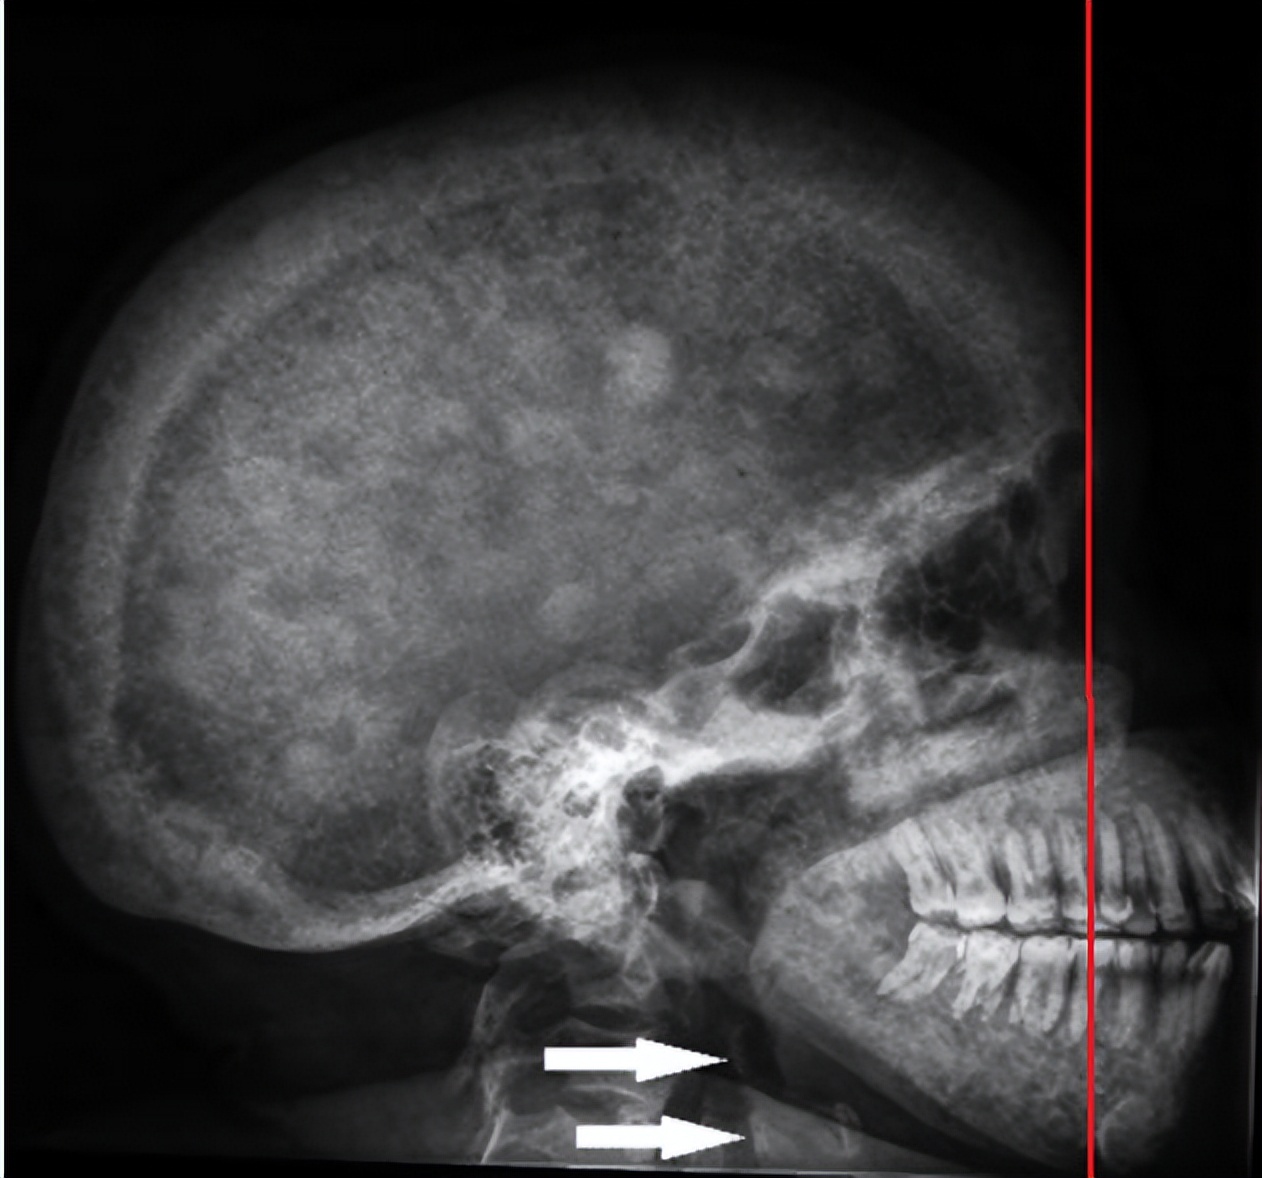

先来看几张图片,下面这位患者的面容有什么特殊吗?嘴那一块地方是不是比较大,且凸,这是由于肾性骨病长期控制不佳而形成的“狮面征”。

图片来源:Oral Manifestations of Chronic Kidney Disease and Renal Secondary Hyperparathyroidism: A Comparative Review. J Vet Dent. 2015.

从影像学检查,我们可以看得更清晰:上颌骨向前向下整体增大、下颌骨垂直向增大,导致面部向前突出、向下增大。

但如果放置不管的话,情况会越来越严重,随病情进展可出现骨痛,如会感觉足跟、腰背、髋部、下肢关节或全身多关节痛。还会造成病理性骨折、骨骼畸形。甚至发展为“狮面人”、“退缩人”,就是开始那几张图。